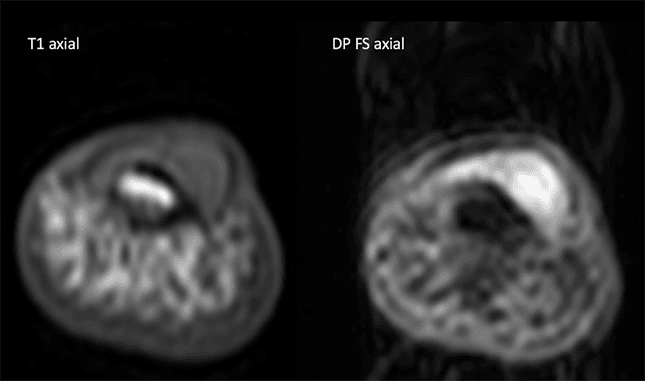

Paciente do sexo feminino, 47 anos, com lesão nodular dolorosa subungueal no I dedo há meses. Relata aumento da sensibilidade nesta região, especialmente no frio.

Imagens